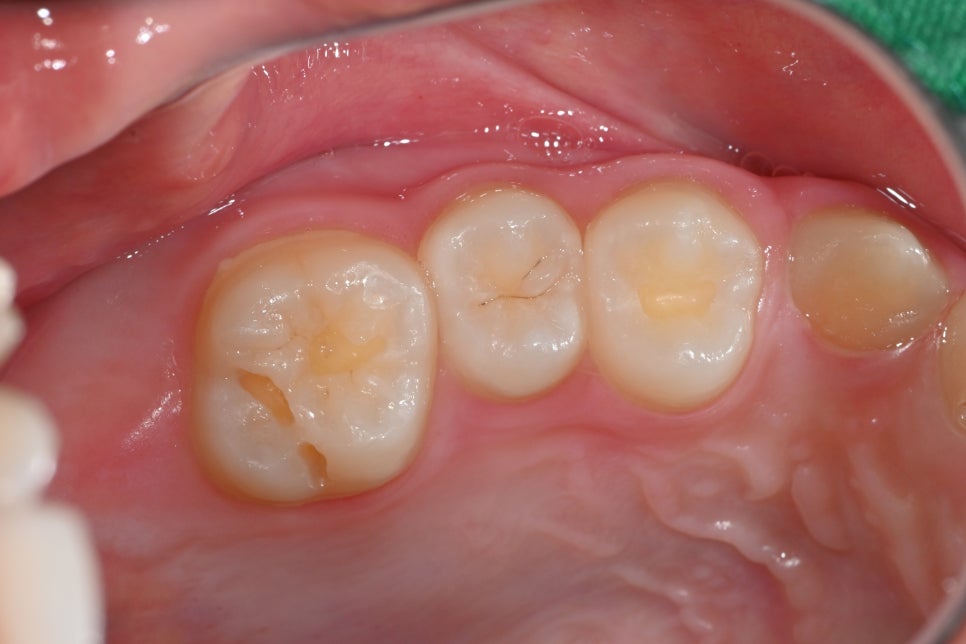

🛠 During Treatment Photo

This shows the process of cleaning the cavity area and preparing for resin restoration.